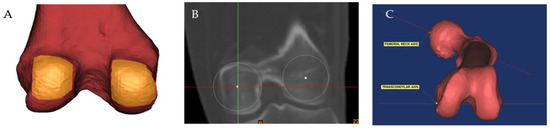

| Lesser trochanter version | 38.54° ± 7.86° | 16.99° to 54.38° | 0.98 | 0.98 |

| Femoral anteversion | 11.84° ± 10.06° | −17.63° to 43.98° | 0.99 | 0.99 |